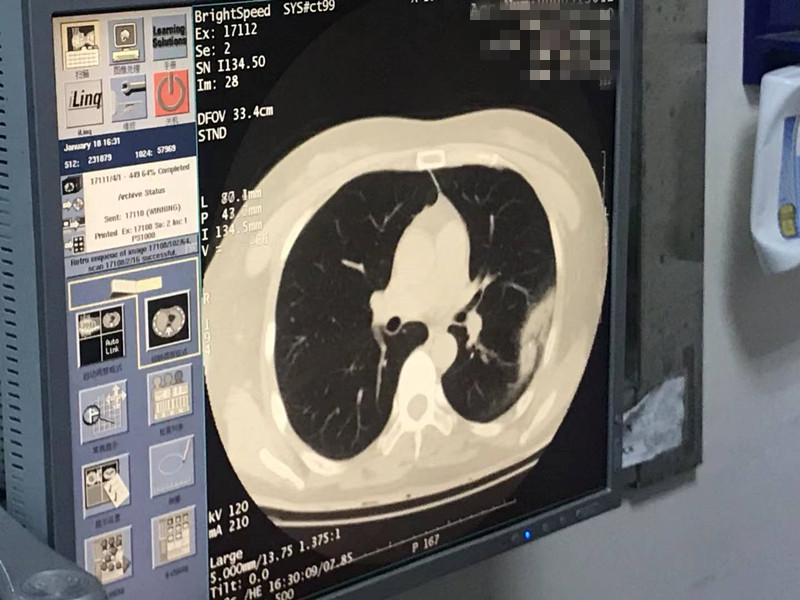

2021年1月份肺部氩氦刀手术